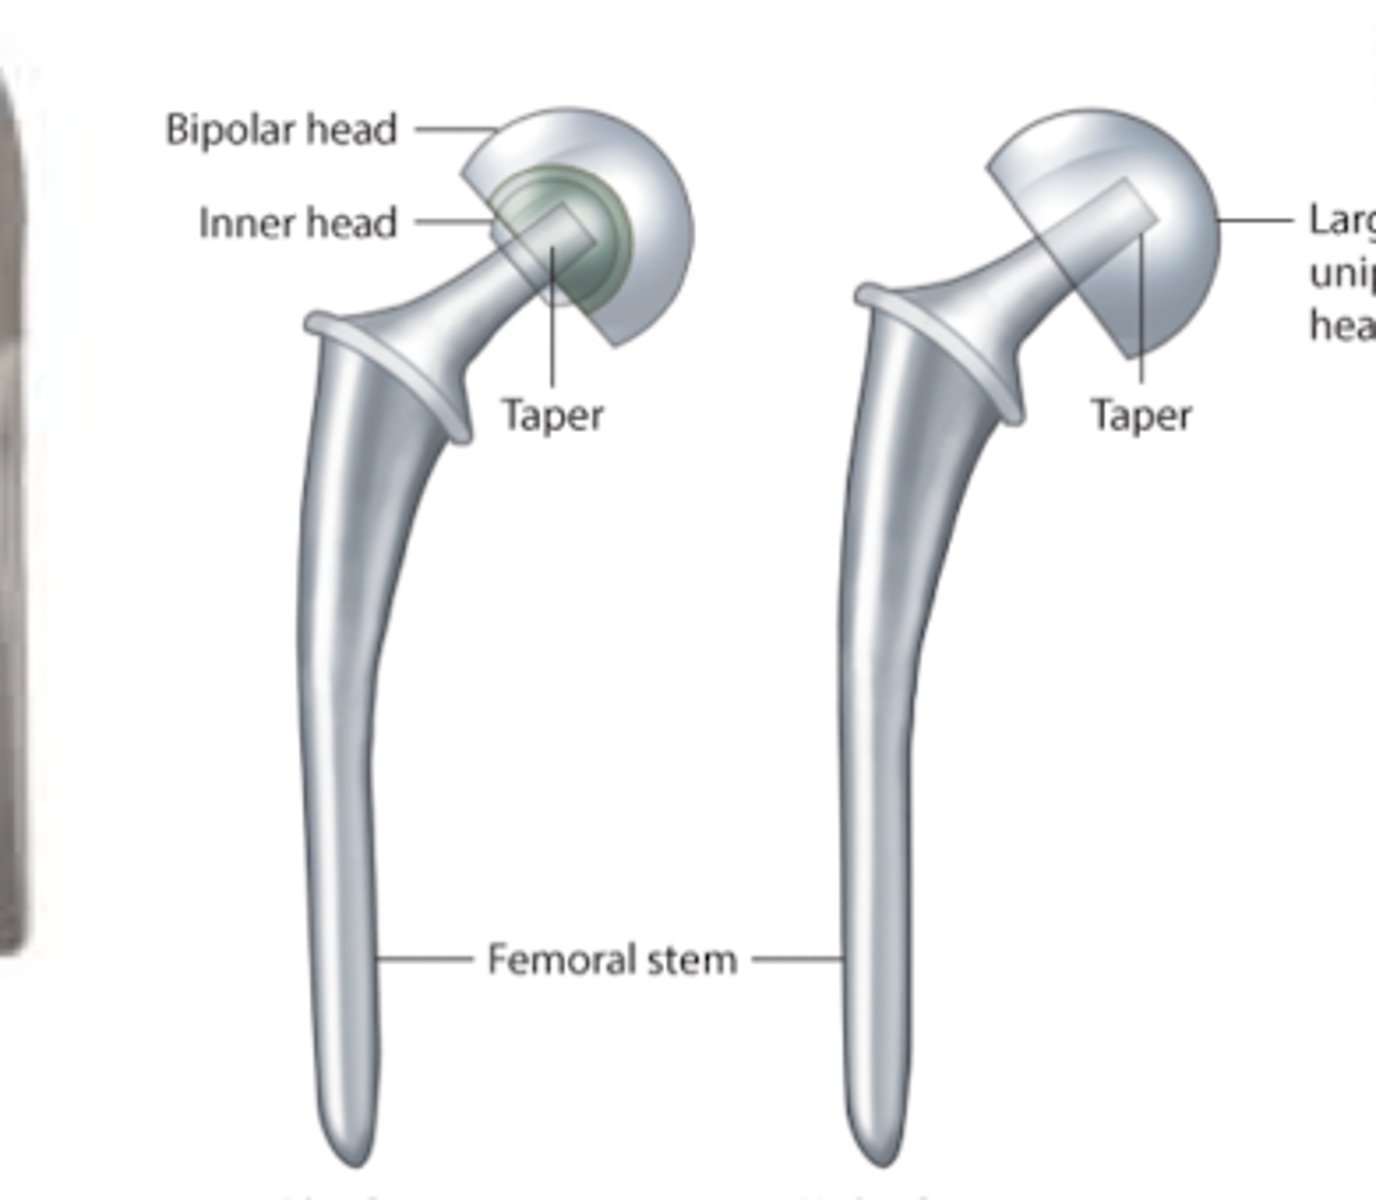

Hip OA

L: bipolar hemiprosthesis

R: unipolar hemiprosthesis